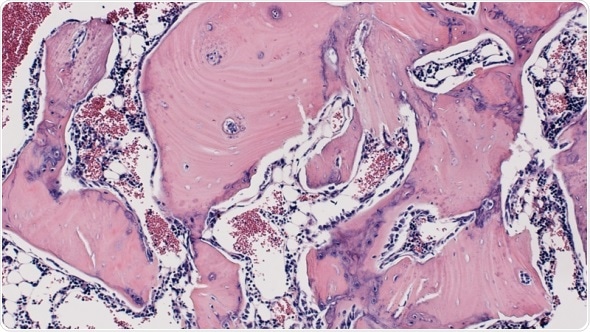

Bone formation in the rat spine. Credit: Aaron James, Johns Hopkins Medicine

After four weeks, the researchers studied the rats' spinal tissue and observed continued high levels of the WISP-1 protein. They also observed new bone forming, successfully fusing the vertebrae together, whereas the rats not treated with stem cells making WISP-1 did not show any successful bone fusion during the time the researchers were observing.